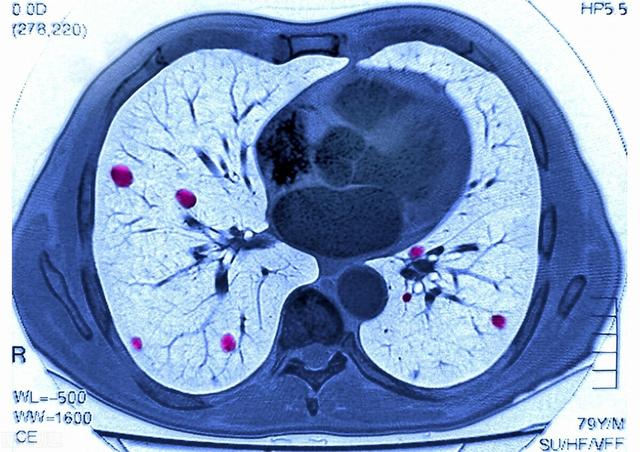

がん細胞は恐ろしいもので、脳転移や肝転移など、血管やリンパのあるところならどこにでも転移する。

このような巨大な肝転移が多発した場合、コントロールできなかったり、治療に反応しなかったりすると、短期間で進行する可能性がある。

(3) 腫瘍転移

進行した肺がんは、体内のさまざまな臓器に多発転移を起こすことがある。 肺がんは脳、肝臓、骨格椎体系に転移することが多く、脳転移は頭蓋内圧亢進症を引き起こすことがある。 脳のスペースが限られているため、がん細胞が増殖すると脳ヘルニアや頭蓋内圧亢進症を引き起こし、生命を脅かすことになる。椎体転移は、病的骨折や神経の圧迫を引き起こし、麻痺や死に至ることもある。多発性肝転移は、肝機能障害や肝不全を引き起こす可能性があります。

4.腫瘍転移、多臓器不全:肺癌の末期には様々な臓器への転移が起こり、患者に大きな苦痛を与える。肺癌患者は胸膜、脳、副腎、肝臓、骨、心膜などの臓器に転移し、多臓器不全を引き起こし、患者の死に至ることもある。